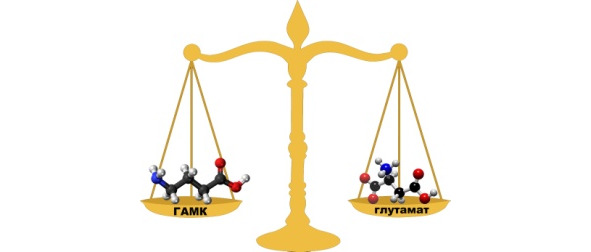

Основными нейромедиаторами в мозге (мы говорим о центральной нервной системе) являются глутамат (возбуждающий нейронную активность и улучшающий проводимость электрических импульсов – он участвует во всех мозговых процессах примерно на 40%) и ГАМК (гамма-амино-масляная кислота, тормозящая или препятствующая проводимости нервных импульсов, участие которой в мозговых процессах также примерно 40%). Качественная работа мозга – это постоянный тонкий динамический баланс между работой глутамата и ГАМК. Если он нарушается в сторону глутамата, возникают нарушения сна, тревожность, шизофрения, эпилепсия. Наш мозг, действительно, может обрабатывать множество информации, но запоминается далеко не все. В первую очередь запоминается то, что часто повторяется или имеет сильное эмоциональное подкрепление (то есть с участием других нейромедиаторов). Остальная информация считается лишней («шумовой») и, чтобы энергозатраты были меньше, ГАМК блокирует работу нейронов, вызывая расслабление.